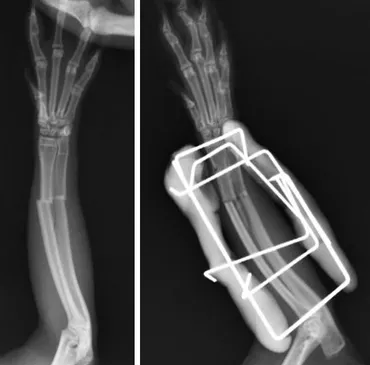

ウサギの骨折治療におけるPEEK材料を用いた研究についてです。

従来の治療法の課題と、新たな可能性を探ります。

✅ ウサギは骨が脆く、犬や猫よりも骨折しやすく、複雑な割れ方をする傾向がある。

✅ 治療法として、ギプスや手術があるが、ウサギの骨の特徴から従来の固定術は困難な場合が多い。

✅ 当院では、創外固定法を積極的に行っており、足の切断が必要と診断された症例でも治療できる可能性がある。

Fukuda N氏の研究は、ポリ(エーテルエーテルケトン)(PEEK)の表面リン酸化と微細粗さの相乗効果が、ウサギ脛骨における骨接合を促進することを示しました。

この研究は、骨接合を促進し、より効果的な治療法を開発するための重要な一歩となりました。